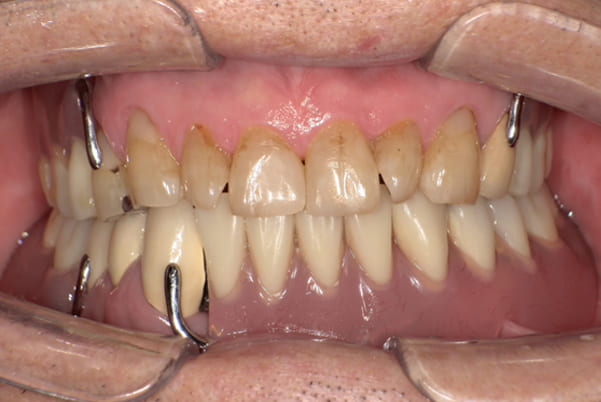

症例レポート[CASE.02]

- 男性(60代)

- 入れ歯がカパカパする、歯がぐらぐらして痛い、食いしばれない

- 上顎精密総金属床総入れ歯

- 下顎精密金属床部分入れ歯

上の前歯が重度歯周病により動揺し、残せない状態のため、入れ歯も動揺がありました。

ご自身の歯に負担の少ないバネ、また見た目も改善

バネをかける歯は繋げることで強度を増し、歯への負担を軽減し、歯の寿命を長くする設計へ。

バネがかかる歯の被せ物は、歯への負担を減らし、入れ歯が動きにくいようになる形態をあらかじめ付与することで、より入れ歯の機能が高まります。

治療を行う際、被せ物や入れ歯は、別々に考えるのではなく、一口腔単位としてお口全体のことを考え最良の治療計画を立てることが歯の寿命、機能効果を向上させるため、専門医としてこのことは常に心掛けて治療を行っています。

残りの歯に負担がかからないよう、被せ物と入れ歯の一体化を図った入れ歯

治療前は上下奥歯の入れ歯が削れていることで、かみ合わせが低くなり唇もつむった状態でした。

かみ合わせを適切な高さに戻したことで、本来の自然な口元へ。